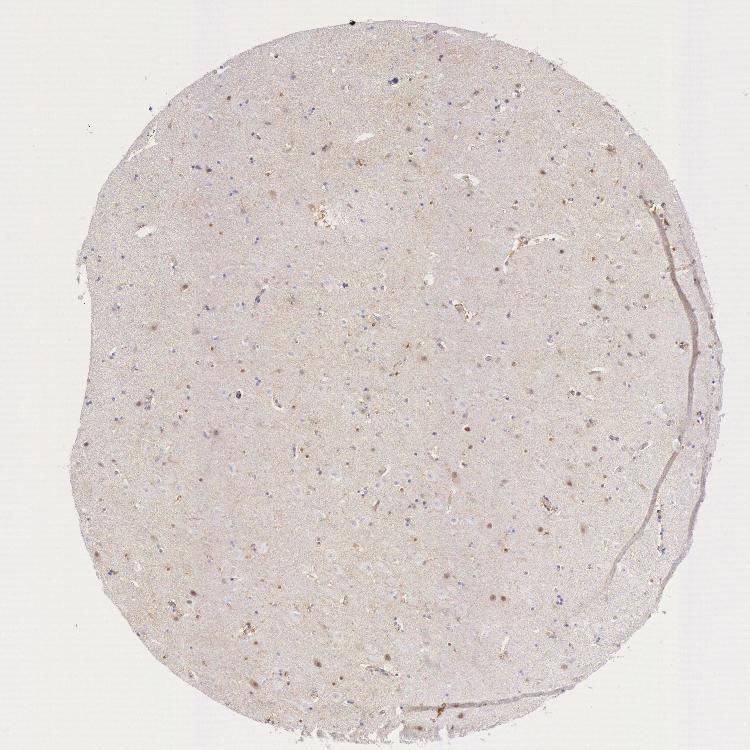

HIPPOCAMPUS - Antibody stainingi

Antibody staining in the annotated cell types in the current human tissue is reported as not detected, low, medium, or high, based on conventional immunohistochemistry profiling in selected tissues. This score is based on the combination of the staining intensity and fraction of stained cells.

Each image is clickable and will lead to virtual microscopy that enables deeper exploration of all samples and also displays staining intensity scores, fraction scores and subcellular localization as well as patient and tissue information for each sample.

Antibody HPA001231Antibody CAB004492

Glial cells LowLow

Neuronal cells Not detectedNot detected